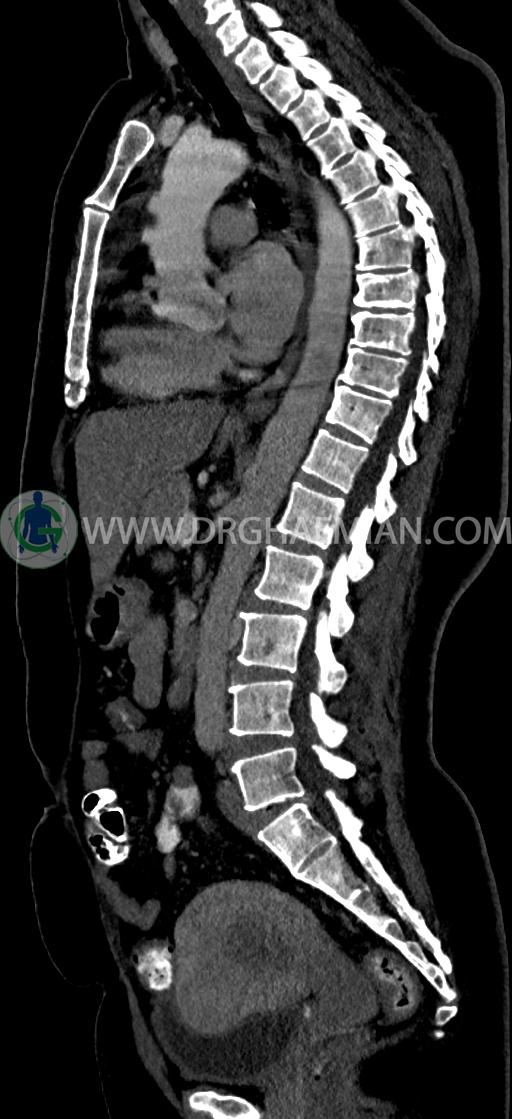

سی تی اسکن شکم و لگن یکی از روش های تصویربرداری با سی تی اسکن است. این روش با استفاده از اشعات ایکس تصاویر عرضی از ناحیه شکمی و لگنی ایجاد میکند. در این کیس سی تی اسکن هیپراستوز اسکلتی ایدیوپاتیک منتشر (DISH)، فیبروم اینترامورال، هرنی سوپرا امیلیکال دیده می شود.

در سي تي اسکن اسپيرال ريه و مدياستن-شکم و لگن با کنتراست خوراکی و وريدی (مولتي ديدکتور 16 با مقاطع ظريف و بازسازي هاي ساژيتال و کرونال) :

–Bridging osteophyte در مهره هاي توراسيک مطرح کننده DISH همراه با کيفوز مشهود است.

–lumbosacral transitional vertebrae

-فيبروم اينترامورال- ساب سروزال به سايز 35mm در قدام فوندوس با اثر فشاري بر ديواره فوقاني مثانه